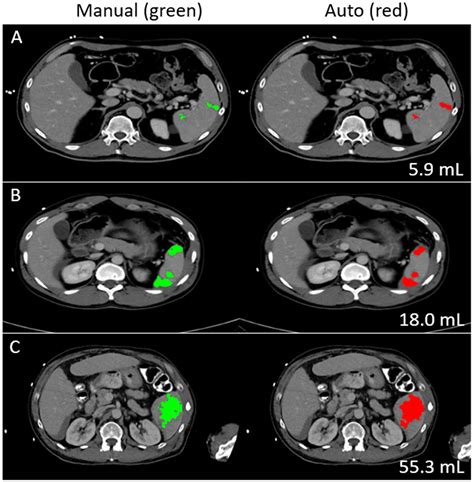

• Imaging Tests: Imaging tests such as CT scans are crucial for visualizing the spleen and assessing the extent of the injury. These tests provide detailed images that help in Splenic Laceration Grading.